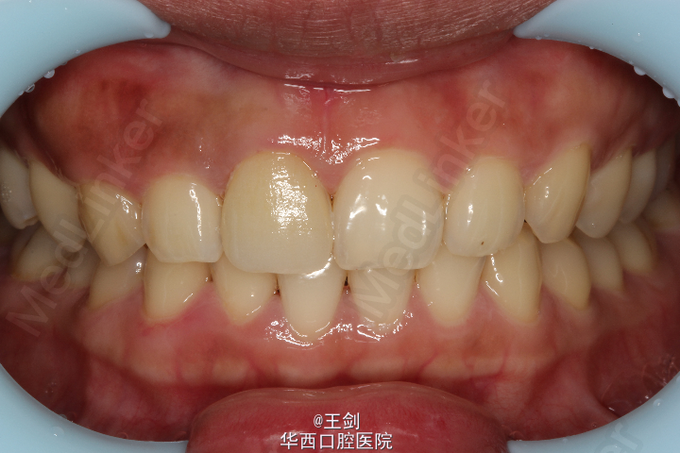

CAD/CAM瓷贴面修复一例

主诉 病史

11牙因外伤缺损,未露髓。

查体 辅查

牙髓活力测试正常,X光片未见根尖暗影,叩痛(-)

拟行CAD/CAM贴面修复11牙,当天备牙,当天戴牙